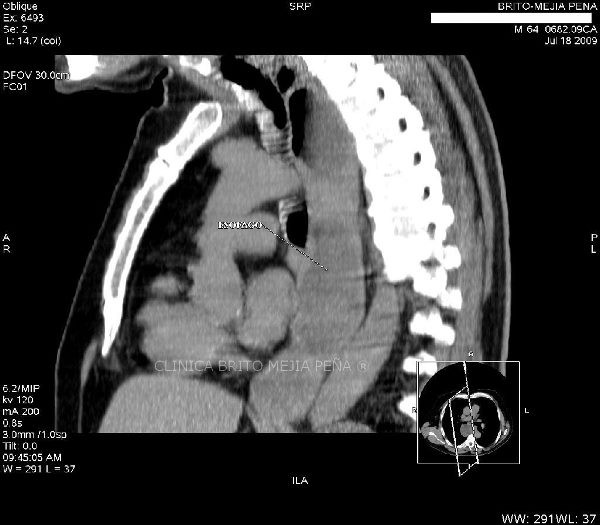

Tumor de esófago oblicua